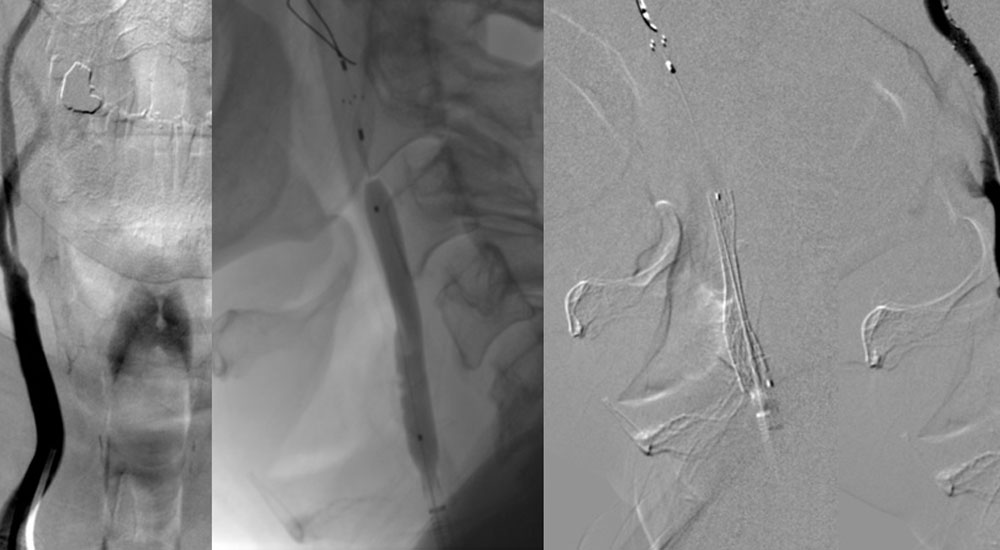

Digital Subtraction Angiography (DSA)